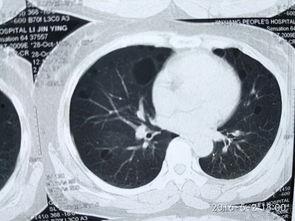

为了让你更直观地了解肺上界叩诊,我找到了一些专业的视频资料。在这些视频中,你可以看到医生们是如何操作的。他们手持木槌,在患者的胸部轻轻敲击,然后仔细聆听声音的变化。有时候,医生还会在患者的背部进行叩诊,以便更全面地了解肺部情况。

肺上界叩诊的主要目的是检查肺部是否有异常,如肺炎、肺结核等。